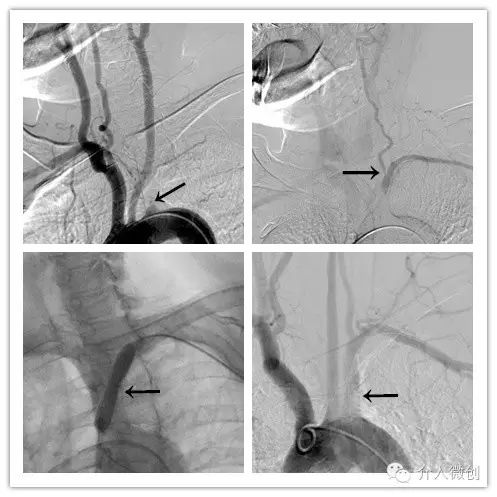

最近老张左上肢活动后出现头晕明显加重,伴左上肢乏力、麻木。彩超检查发现左侧锁骨下动脉起始部闭塞,并见左侧椎动脉逆流。随后老张在介入科医生建议下行左锁骨下动脉成形术,术后头晕症状即刻得到缓解。

经球囊扩张及支架置入后血流恢复通畅,患者头晕症状即刻缓解。